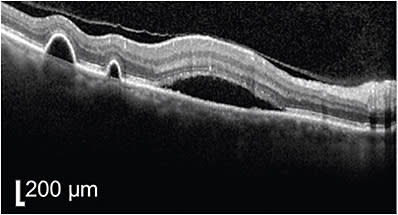

The 6-week check up following PDT showed complete resolution of subretinal fluid, but persistent RPE clumping or plaques subfoveally (Figure 2). Vision remained 20/20 throughout the observation period as well as status post PDT, and the patient reported complete resolution of metamorphopsia.